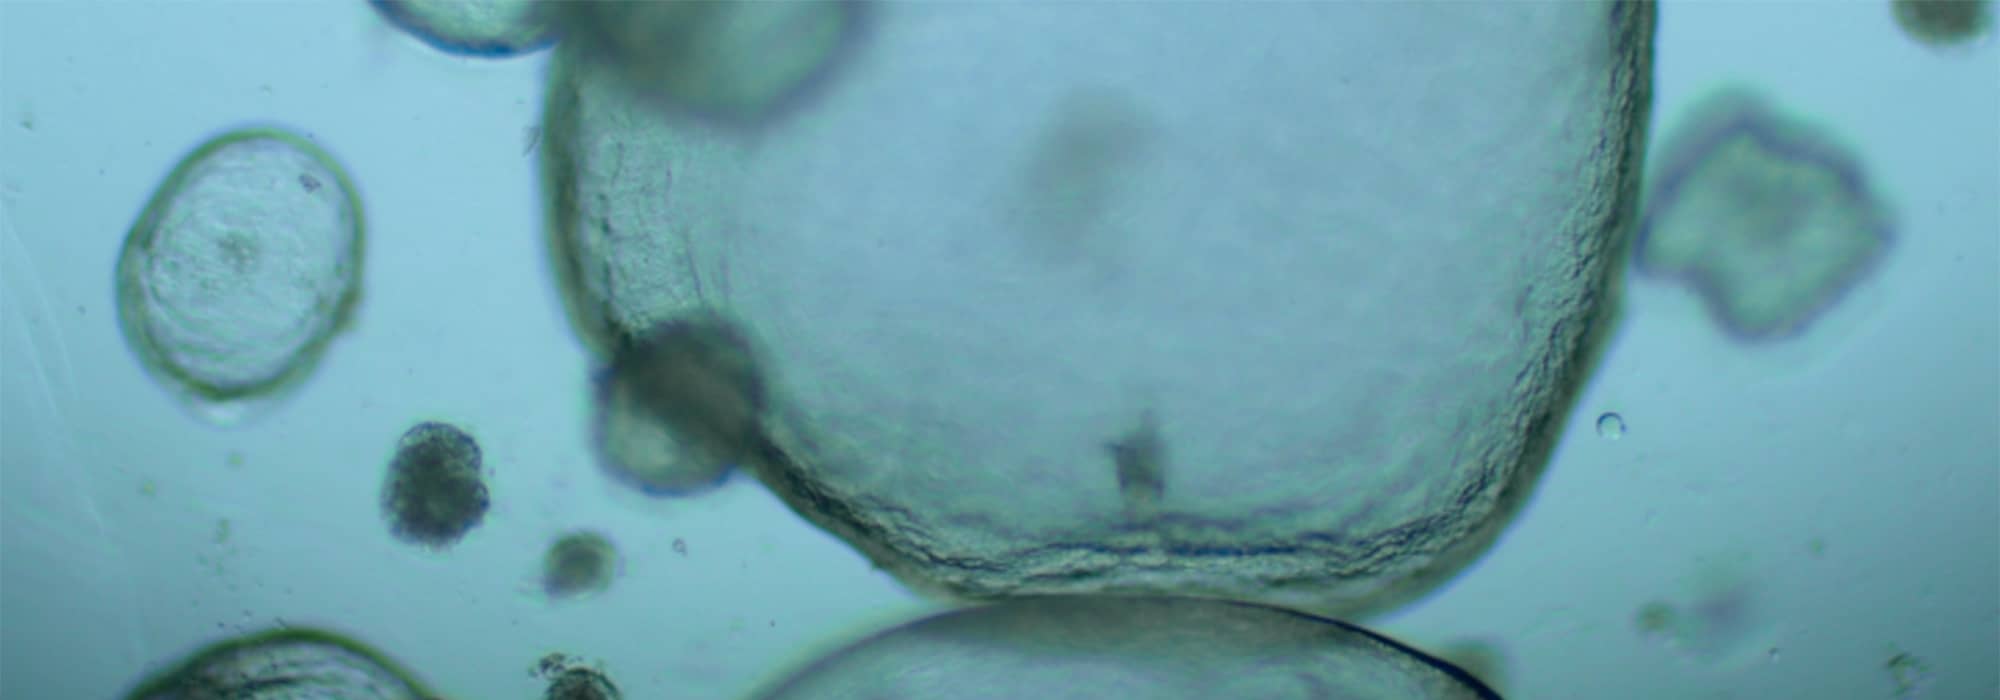

Développement et analyse de modèles organoïdes de trompes de Fallope humaines

Les chercheurs du laboratoire Développement embryonnaire, fertilité et environnement (DEFE) ont mis au point, en collaboration avec l’Institut de recherche en santé digestive (IRSD), des organoïdes humains de trompes de Fallope. Le modèle obtenu a montré un bon niveau de différentiation avec des cellules spécialisées.

Les chercheurs ont ensuite développé un système de coculture de ces organoïdes avec des spermatozoïdes humains conservés à la Germethèque afin d’étudier leur pouvoir fécondant. Ce système prometteur a permis de montrer que les spermatozoïdes conservaient leur mobilité pendant plusieurs jours, à des niveaux supérieurs à ceux obtenus au cours des opérations médicales d’assistance à la procréation. Il offre en outre la possibilité d’étudier en détail les interactions entre l’épithélium tubaire et les gamètes ou embryons, de mieux comprendre certaines infertilités et d’améliorer les techniques d’assistance médicale à la procréation.

Pour en savoir plus : Gatimel N. et al. (2025). Human fallopian tube organoids provide a favourable environment for sperm motility. Human Reproduction, 40(3):503-517.